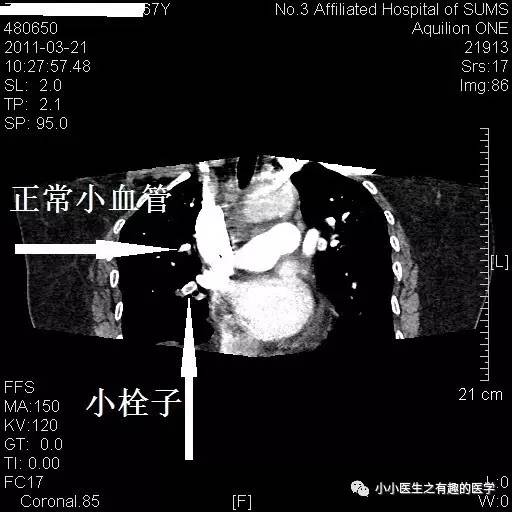

病例一:

女性,老年,胸痛伴气喘20余天。1周前出现双下肢浮肿。查体:双下肢足背浮肿。D-二聚体:5.10 ug/mL。心脏彩超:肺动脉收缩压RVSP:39mmHg。B超:双下肢深静脉血栓形成。

左肺动脉血栓。

小血栓。

右边也有血栓。

最终诊断:肺栓塞。